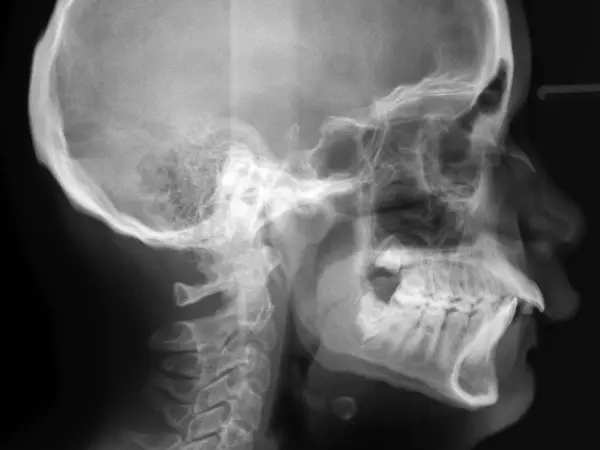

An open bite occurs when the top and bottom rows of teeth don't touch when the mouth is closed. Open bites can occur in the front of the mouth (anterior open bite) or the back (posterior open bite), although front-teeth open bite is more common. Genetics or prolonged thumb-sucking in childhood are common culprits of open bites.

An overbite is a too-large overlap between the top teeth and the bottom teeth. The top teeth hang too far over the bottom teeth: in severe overbites, the bottom teeth may even make contact with the roof of the mouth, causing damage to the tissue and bone. While a small overbite is normal in a proper bite, too large overbites are considered malocclusions and should be treated with orthodontic care.

Crossbite, or underbite, is a malocclusion when the top and bottom rows of teeth overlap improperly. The bottom teeth are set past the top teeth when the jaw is closed. This can occur in the front or back teeth, and can create a combination of overbite and underbite, or underbite and open bite.

An overjet is a condition where there's a large horizontal gap between the top and bottom teeth when the mouth is closed. This gap makes the front teeth stick out. This condition is often called "buck teeth." A small overjet is normal, but a larger one requires orthodontic treatment.